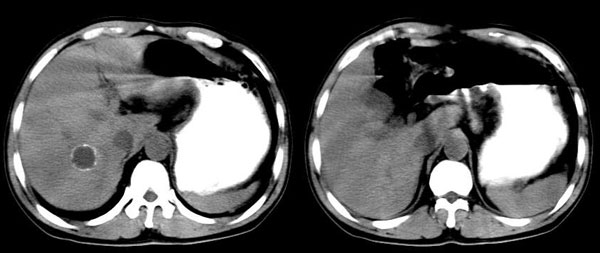

男,44岁,解黒便18天,胃镜:胃小角溃疡性质待查,表浅性胃炎。b超肝右叶占位。ct平扫肝右叶见一囊性占位,ct值:18hu,壁呈带状高密度钙化,增强扫描未见强化。考虑:囊肿?但壁钙化第一次见,不能确定,病人是南方石山地区,未到过牧区,能否排除包虫?

平扫ct值:

18hu.

增强扫描:病灶未强化。

延时4分钟